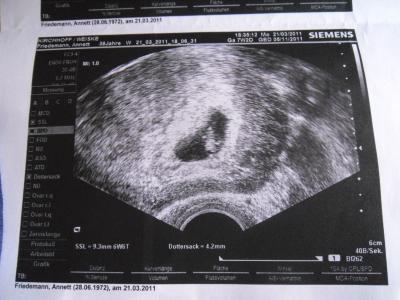

Hallöchen alle zusammen , war am Montag zur VU , Mutterpass wurde angelegt, muss alle 14 tage zur Vorsorge da ich als Risikoschwangere eingestuft bin. Soweit war alles okay , Herzchen hat schon geschlagen. Leider hab ich in der Nacht wahnsinnige Magenkrämpfe bekommen und gereiert......naja , war nicht mehr feierlich.Inzwischen kann ich wieder was festes essen , ne leichte latente Übelkeit ist immer da. Ich wünsche euch einen sonnigen Tag.. LG Anna

Bild zu Erste VU + Bild - Forum für November - Mamis

Super! Ganz tolles Zwergenbild! Ich freu mich auch schon auf mein erstes... Darf ich fragen warum du als Risikoschwangerschaft eingestuft worden bist...? Liebe Grüße